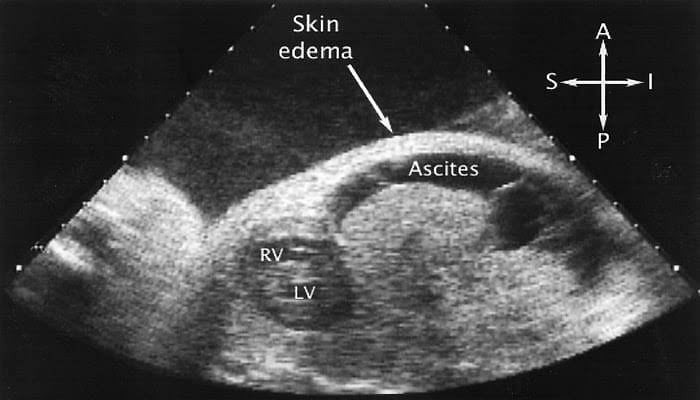

* குழந்தைக்கு ஹைடிராப்ஸ் ஃபீடாலிஸ் (Hydrops Fetalis) பாதிப்பு இருக்கும்போது.